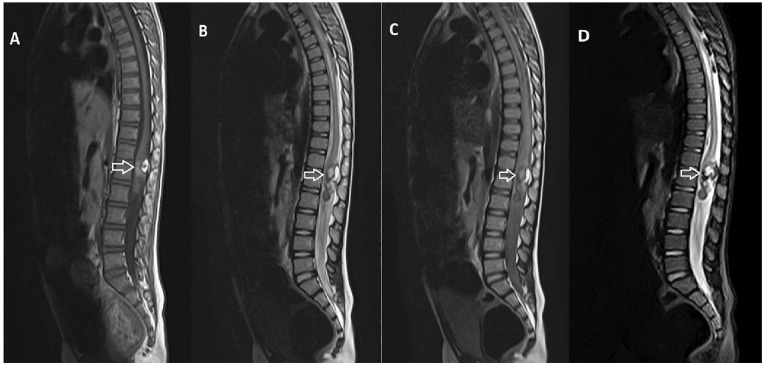

脊柱畸胎瘤虽然在脊柱肿瘤中很少见,但在硬膜内-髓内病变的鉴别诊断中应予以考虑,特别是在出现泌尿和粪便症状的儿童中。全面的影像学评估,包括CT和MRI的特征性发现,如囊性和实性成分,脂肪组织的存在,以及相关的脊髓异常,如鼻咽形成,可以帮助早期诊断。手术切除仍然是治疗的主要方法,及时干预对于预防进展和减轻患者的症状至关重要。在这里,我们讨论一个病例硬膜内-髓内畸胎瘤在一个6岁的儿童谁是及时诊断通过CT和MRI和治疗全手术切除。

Spinal teratomas, though rare among spinal tumors, should be considered in the differential diagnosis of intradural-intramedullary lesions, especially in children presenting with urinary and fecal symptoms. Comprehensive imaging evaluation, including CT and MRI with characteristic findings such as cystic and solid components, the presence of fatty tissue, and associated spinal cord abnormalities like syrinx formation, can aid in early diagnosis. Surgical resection remains the mainstay of treatment, and prompt intervention is crucial to prevent progression and alleviate symptoms in affected patients. Here, we discuss a case of an intradural-intramedullary teratoma in a 6-year-old child who was timely diagnosed using CT and MRI and treated with total surgical resection.